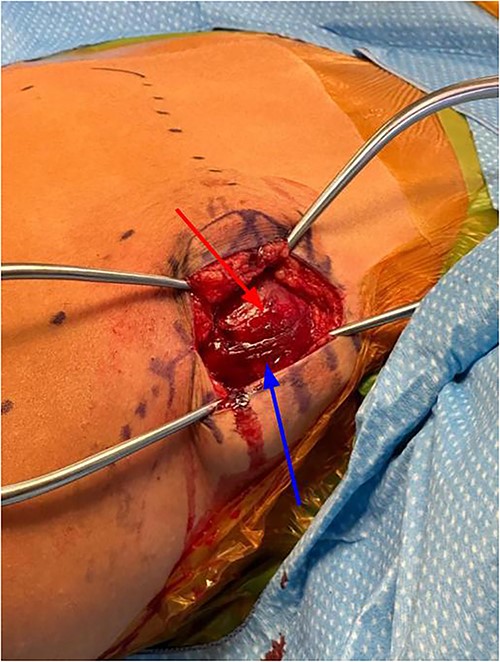

Subcutaneous tissue was divided with the electrocautery. Investing fascia over the trapezius was identified and the division between the superior and middle fibers of the trap was identified. The raphe between the superior and middle fibers was then bluntly spread in line (Fig. 3). We then encountered the superior aspect of the ventral lesion on the scapula (Fig. 4). Of note, the majority of levator scapulae fibers were medial to this lesion; however, the most lateral portion of the muscle was overlying the lesion. These lateral fibers were spread in line to expose the pedunculated mass. Blunt dissection was then taken circumferentially around the stalk of the mass to ensure all soft tissue had been freed from the area (Fig. 5). An osteotome was then carefully placed within the wound at the base of the stalk, and the tumor was then removed and sent to pathology for analysis. The stalk remnant was then filed down to a smooth and stable base with a rasp without any significant areas of potential irritation or prominence. The wound was then copiously irrigated with normal saline. Fluoroscopy images demonstrated complete resection of the bony tumor. There was no active bleeding within the wound. The fascia overlying the trapezius muscle and the skin were then closed.

Exposure after scapula has been retracted and lesion was exposed, lesion can be directly visualized.